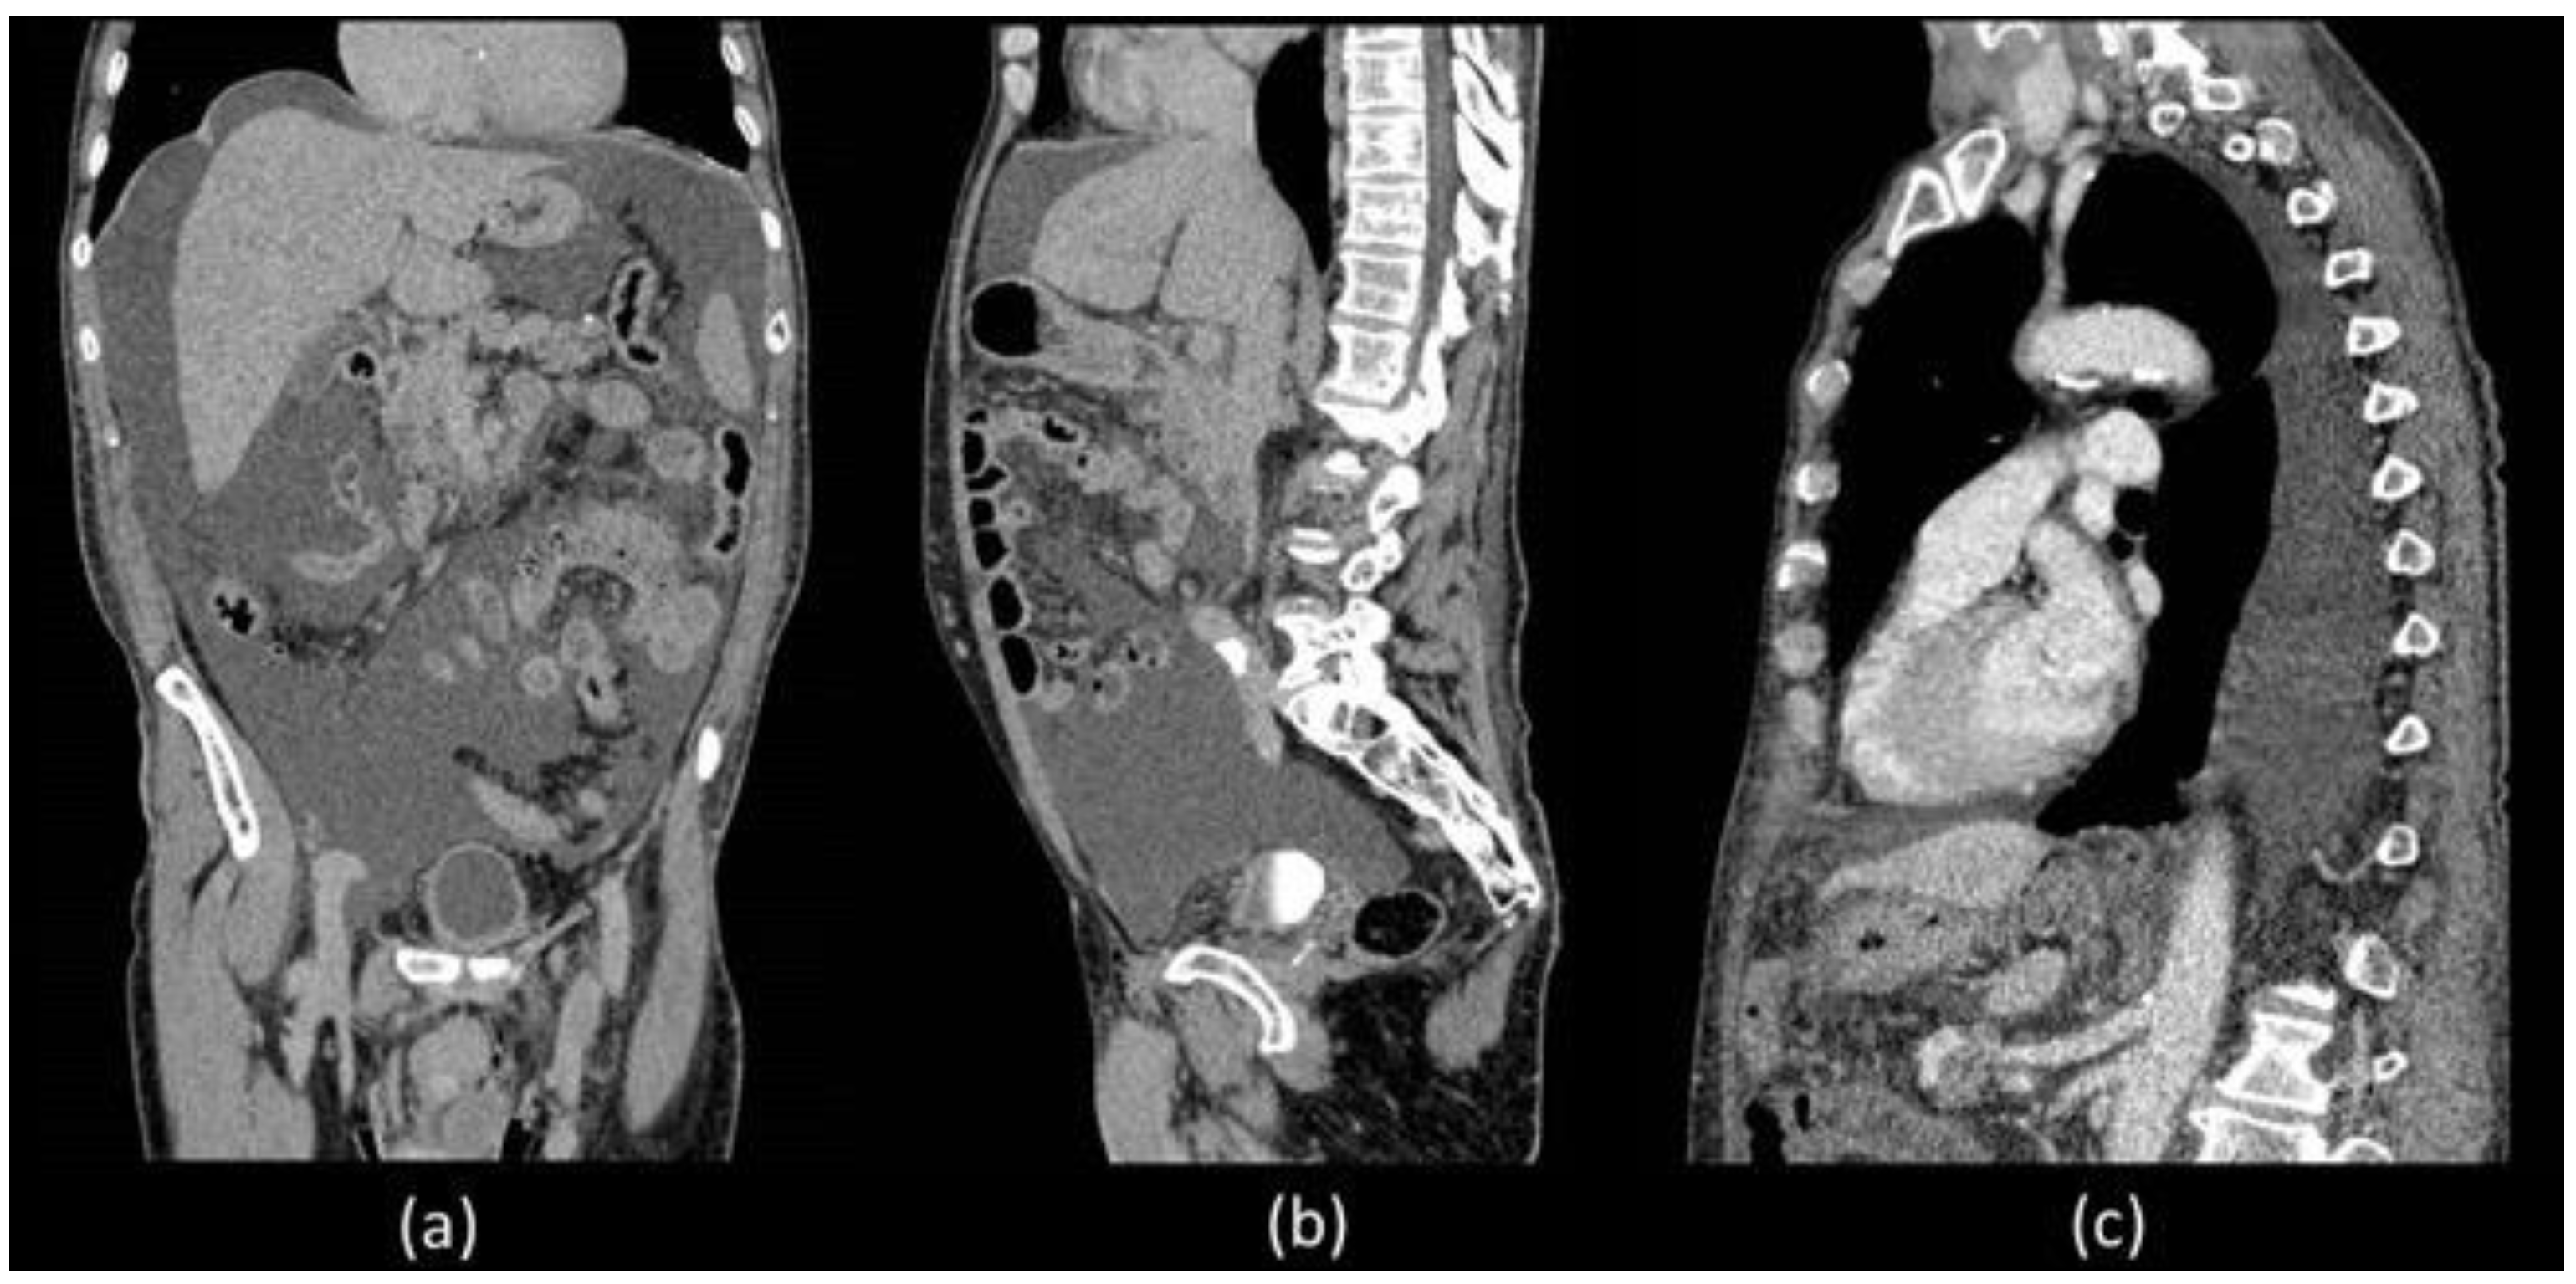

Unfortunately, he was readmitted 7 days later with abdominal distension and dyspnoea. During hospitalization, thorax and abdominal contrast-enhanced CT was performed which confirmed a massive ascites and described the presence of left pleural effusion without the presence of liver diseases (Figure 1).

Figure 1.

Coronal (a) and sagittal (b) abdominal CECT showed massive ascites in supra and inframesocolic recesses. Non-hepatic diseases were recorded. (c) Sagittal thorax CECT demonstrated left pleural effusion.